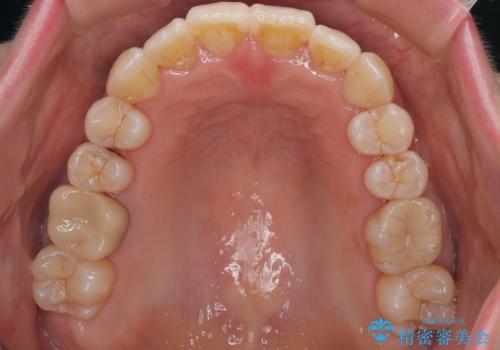

- 上下前歯のデコボコを気にして来院された患者様です。

デコボコは顕著であるものの、口元の突出感は強くないため、非抜歯にて矯正治療を行うこととしました。

装置はワイヤー装置でもマウスピースでも対応可能でしたが、より目立たない装置をご希望とのことで、インビザラインにて矯正治療を行うこととしました。

元々の叢生と歯肉退縮傾向になる歯肉であったため、ブラックトライアングルが目立つことが想定されました。

治療過程でブラックトライアングル改善のため、IPR(歯と歯の間を削る)を活用しました。